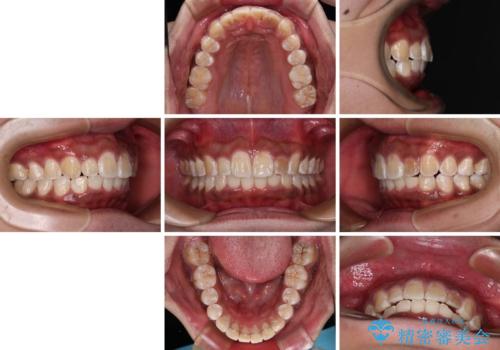

上顎前突とディープバイト ワイヤー矯正での確実に仕上げる

- 深く咬みこみ、前に飛び出した上顎前歯を気にして来院された患者様です。

口元の突出感はあまりありませんでしたが、上顎歯列が全体的に前方にあり、更には下顎歯列が深く咬みこんでいるために、上顎前歯が前方に突出している状態でした。

抜歯は行わず、補助装置を用いて上顎歯列全体を後方移動させ、ワイヤー装置にて奥歯の咬み合わせを改善していくこととしました。